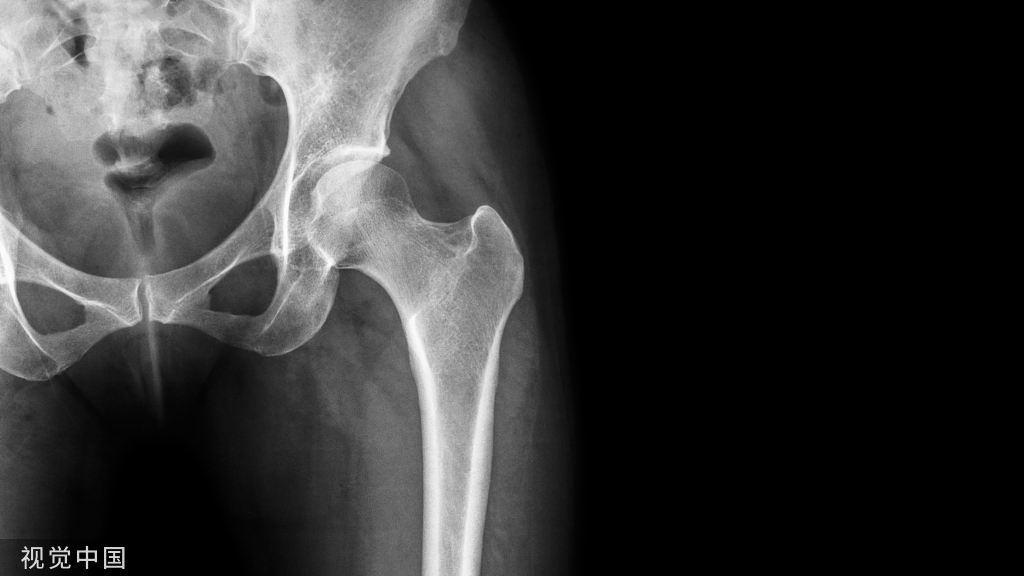

为此,有学者提出采用锁骨钢板+锚钉联合固定的方法,下图所示一例锁骨中段骨折合并同侧IV型肩锁关节脱位患者:

先采用锁骨解剖钢板固定锁骨骨折,复位脱位的肩锁关节后,在喙突置入两枚金属锚钉,并将锚钉自带缝线分别穿过锁骨钢板螺钉孔,在锁骨前方及后方分别打结固定,最后采用缝线直接缝合肩锁韧带及喙锁韧带: